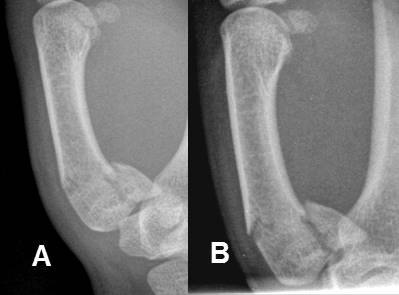

A: y B: Rx lateral de muñeca. Fractura de Colles, con desplazamiento posterior del fragmento distal del radio.